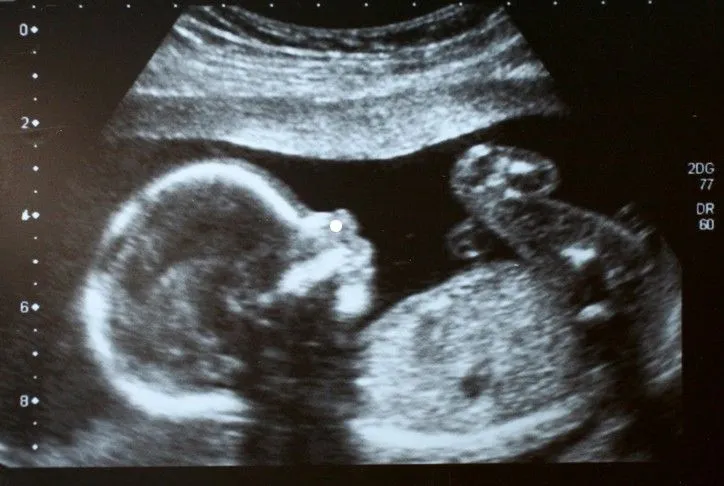

🤔 À NUANCER L’enfant venant d’instinct soigner sa maman c’est croquignolet mais… Le microchimérisme est défini comme une petite population de cellules qui sont originaires d’un autre individu et qui sont dès lors génétiquement distinctes des cellules de l’individu hôte. Les cellules foetales (souches ou immunitaires) migrent au travers du placenta vers les tissus maternels où elles peuvent persister pendant des décennies. https://bit.ly/44TuaMW Ce post présente des effets bénéfiques de cette migration. Les cellules pourraient participer à la réparation tissulaire et à la modulation du système immunitaire maternel, contribuant à la tolérance immunitaire et à la cicatrisation. https://bit.ly/44pCkg5 Mais le post omet de mentionner qu’un excès de microchimérisme foetal est associé à des complications de grossesse (prééclampsie, retard de croissance, diabète gestationnel) et à un risque accru de maladies auto-immunes (lupus, thyroïdite d’Hashimoto, sclérodermie). https://bit.ly/44TuaMW Enfin, prêter à ces cellules une empreinte d’amour, ou dire que l’enfant protège la mère nous emporte dans le domaine des croyances, assez loin de la biologie. https://dumas.ccsd.cnrs.fr/THESES-SU/tel-04715170v1